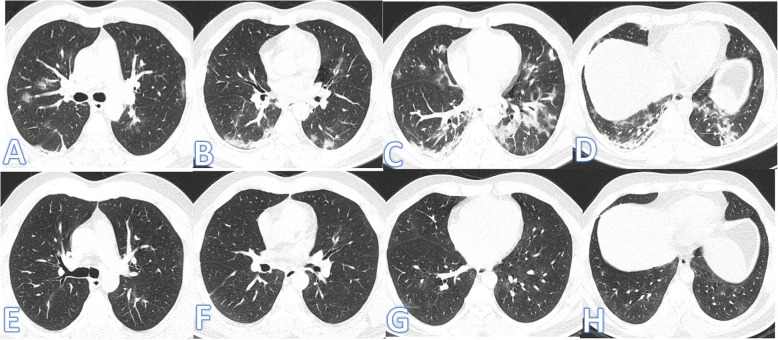

Fig. 3.

Forty-three-year-old male, he has no past medical illness; peak CT severity score 18; consolidation/crazy-paving score 14. He was admitted to the ICU; laboratory results showed lymphopenia, high CRP, d-dimer, and serum ferritin. Steroid was given; length of stay during hospitalization is 65 days. CT after 3 weeks of admission (a–d) showed bilateral GGO with bilateral upper lobe fibrotic bands (arrows) and traction bronchiectasis (orange arrows). Follow-up CT 2 months after discharge (e–h) showed lung fibrosis with parenchymal bands, coarse reticular pattern (arrows), and mild traction bronchiectasis at the anterior segments of both upper lobes (orange arrows).